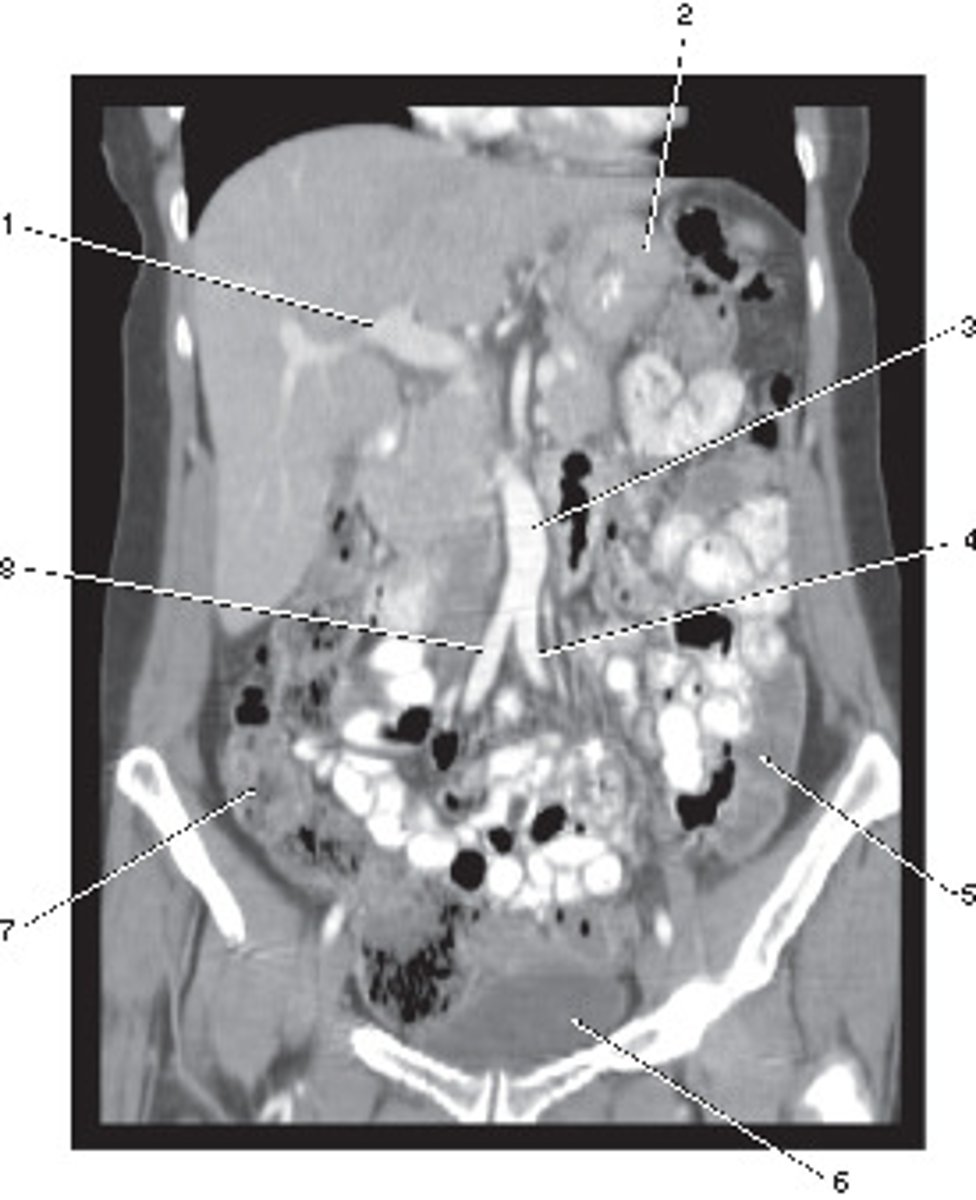

Number 2 corresponds to which of the following?

<p>Number 2 corresponds to which of the following?</p>

Spleen

Number 4 corresponds to which of the following?

<p>Number 4 corresponds to which of the following?</p>

Number 1 corresponds to which of the following?

<p>Number 1 corresponds to which of the following?</p>

Number 5 corresponds to which of the following?

<p>Number 5 corresponds to which of the following?</p>

Corticomedullary;

30-40 seconds after injection,

the corticomedullary phase demonstrates optimal enhancement of the renal cortex with maximum differentiation from the renal medulla

This image of the abdomen was most likely acquired in which in which renal enhancement phase?

<p>This image of the abdomen was most likely acquired in which in which renal enhancement phase?</p>